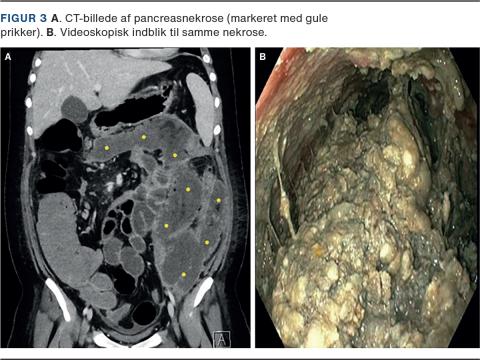

VARD forudgås af perkutan drænanlæggelse i den retroperitonealt beliggende pancreasnekrose (Figur 1) og foregår i generel anæstesi. Under proceduren ligger patienten i rygleje med enten venstre eller højre flanke eleveret afhængigt af nekrosens beliggenhed. Der foretages incision langs drænet, enten subkostalt eller interkostalt, hvorefter der dissekeres til den nekrotiske ansamling. Videoassisteret, med laparoskopisk optik, tømmes kaviteten for løst débris med sug og tænger (Figur 2 og Figur 3). Hvis forholdene tillader det, kan operationen foretages laparoskopisk ved anlæggelse af en gelport (Figur 4), hvorefter kaviteten kan åbnes med CO2-insufflation. Der kan herefter anvendes laparoskopiske instrumenter og foretages endoskopi gennem trokarer. Efter proceduren anlægges der to store skylle- eller bølgedræn i kaviteten mhp. sufficient postoperativ drænage og lavage.